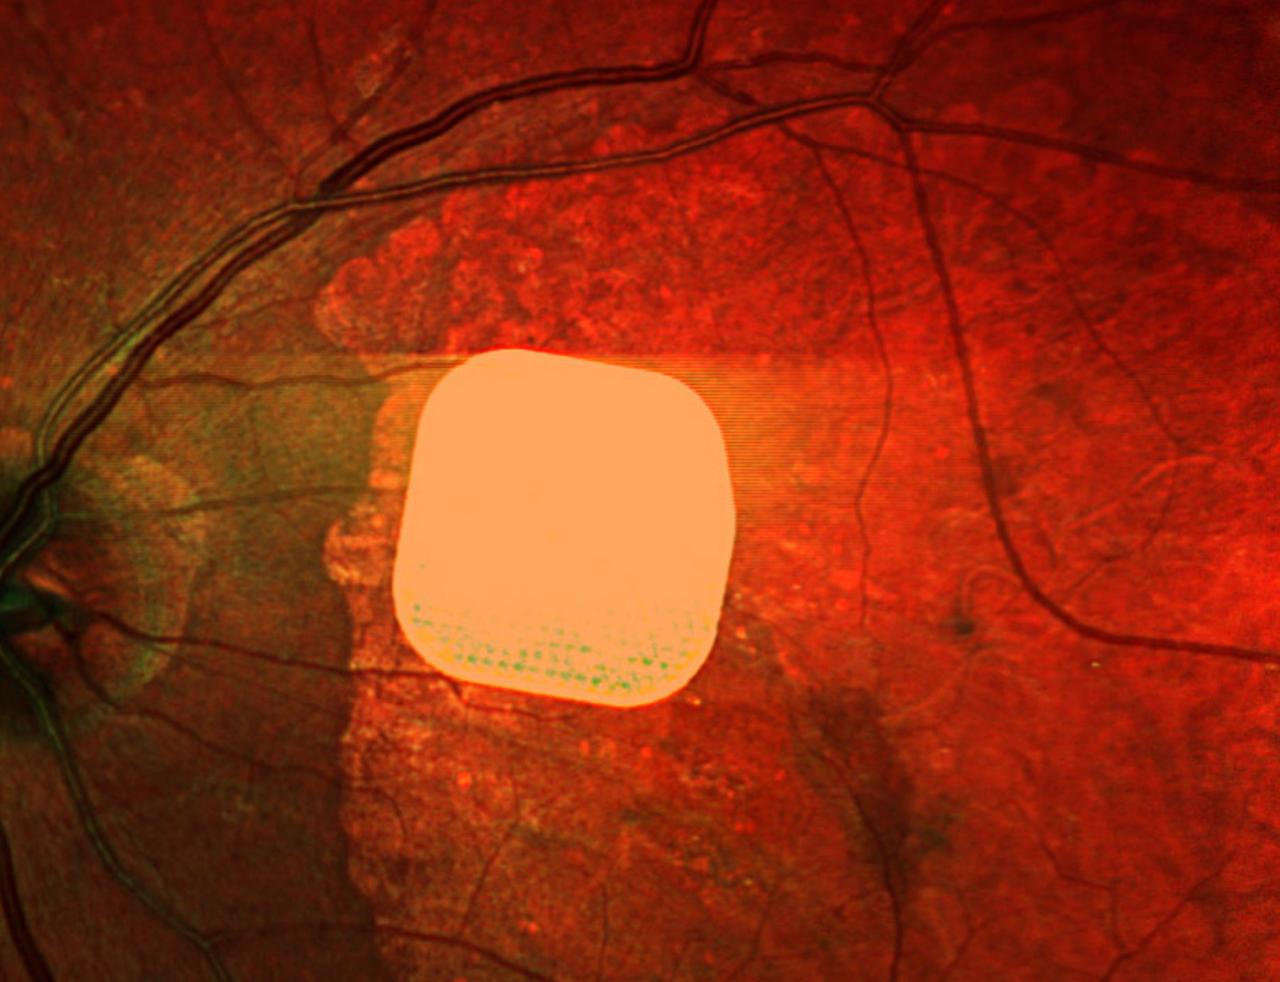

Кровавая барыня

Ученые создали имплант который позволяет вернуть зрение после атрофии сетчатки глаза пишет американский научный журнал NEJM Система фотоэлектрической ретинальной имплантации включает субретинальный фотоэлектрический имплант и очки которые проецируют ближнее инфракрасное излучение на имплант для восстановления зрения в областях центральной атрофии сетчатки Под наблюдением ученых с новым изобретением были 32 человека с атрофией сетчатки глаза За год благодаря импланту у них значительно улучшилась острота зрения говорится в статье Подписаться на РИА Новости экономика Все наши каналы

Ученые изобрели глазной имплантат который поможет слепым пациентам частично восстановить зрение сообщает Financial Times Пациенты с географической атрофией смогут снова например читать заявляют ученые Новая технология включает в себя камеру установленную на специальных очках которые носит пользователь Камера снимает изображения и проецирует их на беспроводной ретинальный имплант размером 2 на 2 мм Затем имплант преобразует свет в электрические импульсы которые передаются в мозг Устройство помогло 81 участников испытаний страдающих от прогрессирующей возрастной макулярной дегенерации Ученые называют это сдвигом парадигмы в лечении слепоты Сайт Страна X Twitter Прислать новость фото видео Реклама на канале Помощь

Слепота ПОБЕЖДЕНА Пожилые люди потерявшие зрение смогли снова увидеть мир вокруг благодаря Prima толщиной с половину человеческого волоса После операции участники смогли не только перемещаться в пространстве и различать объекты но и даже читать обычный текст Микрочип вживляется под сетчатку а подключенные AR очки с камерой передают изображение прямо в мозг через зрительный нерв Ученые называют результат РЕВОЛЮЦИЕЙ в лечение слепоты Наконец то полезный киберпанк trends